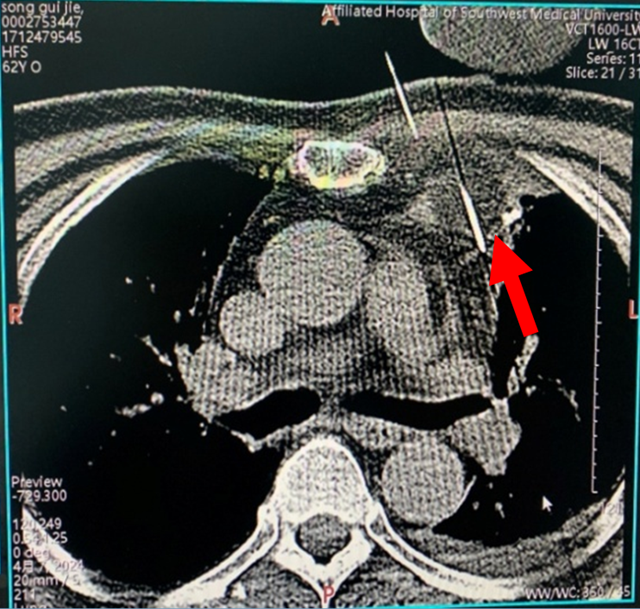

介入科李玉伟教授、胸外科戴天阳教授在影像科漆万银教授的配合下,选择局部麻醉,在CT引导下,精准定位穿刺,冷冻消融针直达肿瘤中心,全程冷冻3个循环,CT扫描见肿瘤达到消融标准,手术顺利,手术过程中患者全程保持清醒,随时与医生保持沟通,患者自诉没有感觉到明显疼痛、胸闷、心慌等不适,整个治疗过程大约半个小时左右。

术后CT扫描